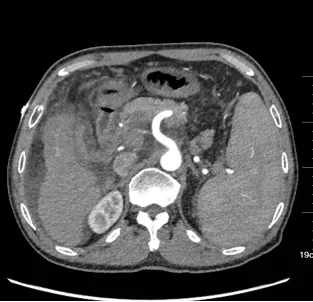

61岁患者高先生,因无明显诱因出现腹胀、恶心、乏力、食欲缺乏等症状,且大便次数增多,每天达7—8次,到其他医疗机构就诊,诊断为肝恶性肿瘤、胃食管静脉曲张。然而,病情并未得到有效控制,22天前高先生突发呕血1小时,紧急到玉溪市中山医院肿瘤诊疗中心就诊。入院后详细检查提示:其血红蛋白量仅为76g/L,血小板计数低至62*10^9/L,同时伴有肝硬化、脾脏增大等严重问题,病情复杂且危急。

(入院时CT)